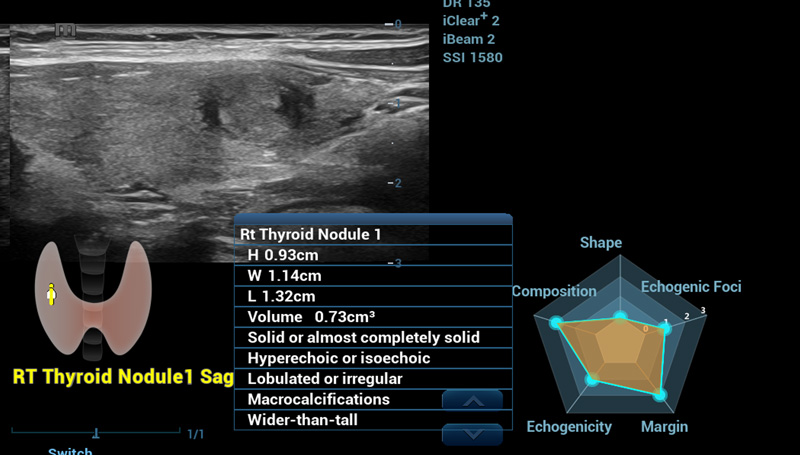

Smart Thyroid

E├®n vlak meer dus meer te zien

Smart Thyroid

Thyroid is een analyse- en rapportagetool voor de schildklier om de klinische routine van schildklieronderzoeken nauwkeuriger en productiever te maken.

Smart Thyroid-nodule